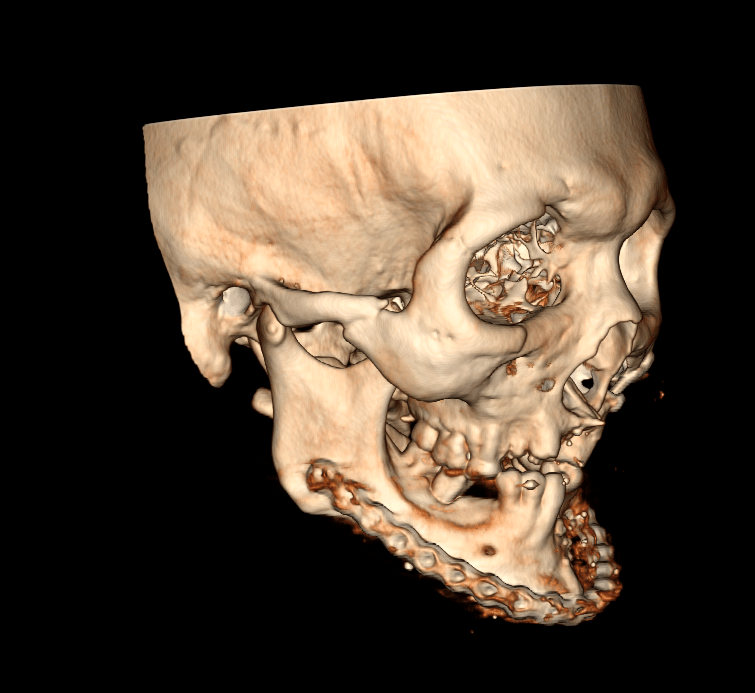

A Tomografia Computadorizada de Mandíbula é um exame de diagnóstico por imagem da mandíbula, a qual é formada por cinco partes e responsável pelo movimento de mastigação.